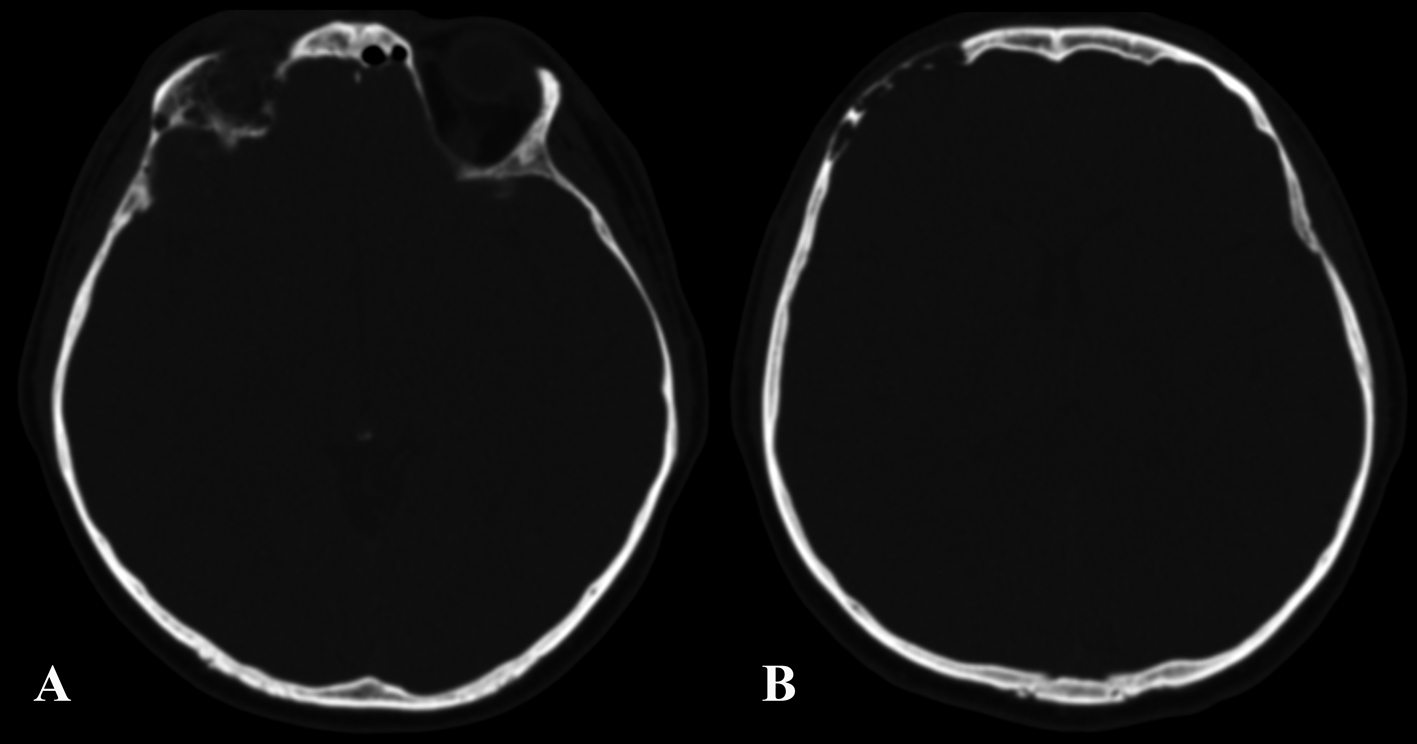

A 37-year-old man was admitted to our hospital complaining of frequent episodes of headache for the past several months. He was followed by the otolaryngologist for sinusitis, but for the persistence of the headache, computed tomography (CT) and magnetic resonance (MR) of the brain were performed. CT scans showed a right frontal calcified lesion e (Fig. 1) and marked enhancement post contrast and MR revealed hypointense lesion in the right frontal lobe with heterogeneous contrast enhancement after Gadolinium administration (Fig. 2). On admission to our department, general, physical and neurological examination found no abnormalities. X-ray scan of the skull revealed an extended geographical area of osteolysis in charge of the frontal squama in the right supraorbital region with involvement of the roof of the ipsilateral orbit and hypoplasia of frontal sinus. A brain CT and MR were repeated and showed no changes beyond those already performed. There were no stigmata or family history of neurofibromatosis.

![]() Click for large image | Figure 1. Pre-operative CT showing the involvement of the right orbital roof (A) and the right frontal bone (B) by the lesion. |